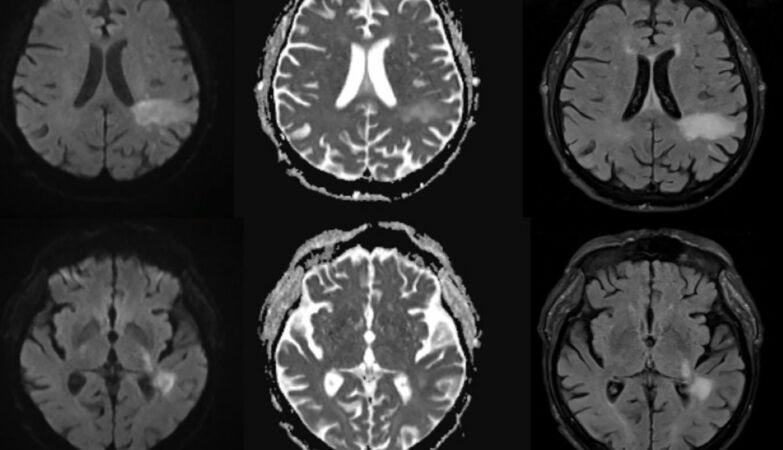

Magnetic resonance imaging of progressive multifocal leukoencephalopathy lesion

PML occurs when the virus undergoes a mutation to a more aggressive form which invades brain cells, destroying the protective myelin sheath around nerve fibers. This leads to severe neurological damage, with symptoms ranging from speech and vision problems to motor dysfunction and seizures. The disease was previously considered almost exclusively associated with profound immunosuppression, as in patients with HIV/AIDS or those undergoing strong immunosuppressive treatments.

The patient, who suffered from stage 5 kidney failure, was admitted with mental confusion, weakness and difficulty speaking. Initially, doctors suspected a condition related to the accumulation of toxins in the blood, common in severe cases of kidney disease. But when her symptoms worsened despite treatment, brain scans revealed lesions characteristic of PML. Later tests confirmed the presence of the JC virus in his central nervous system. The patient died just two days after diagnosis.